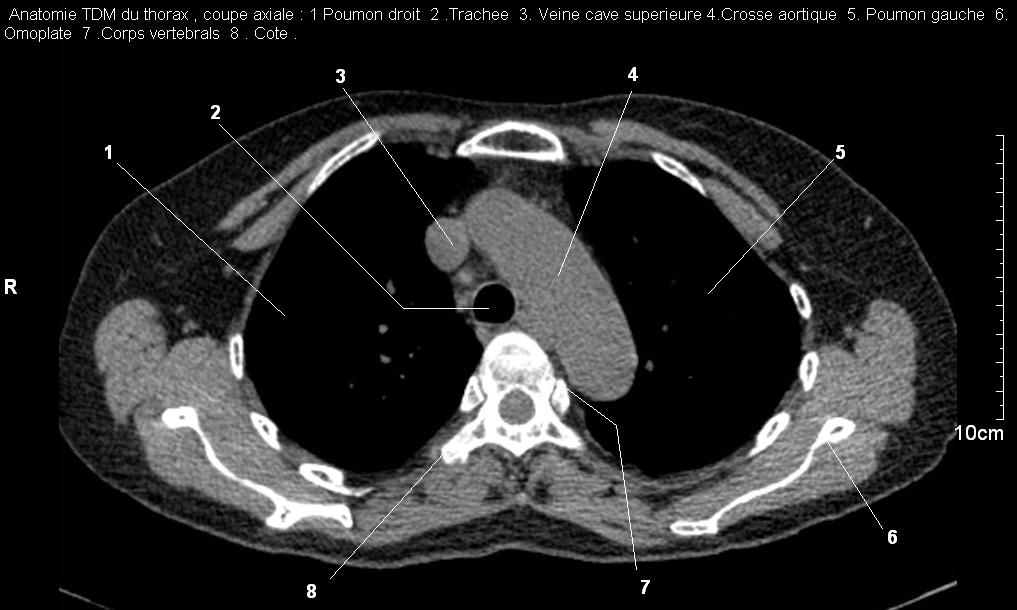

Radioanatomie pulmonaire ( image radiologie

thoracique normale )- La Tomodensitometrie du thorax (

coupes axiales fenetre mediastinale ) |

Les fenetres mediastinales permettre

d'etudier anatomie du mediastin , les structures vasculaires

en coupes axiales de 0,5-1cm sur le thorax . Ceux qui

s'installent travers le thorax de C4 a L1, L2

a n'a pas de contrast et se donnent des resutats

suivantes : |